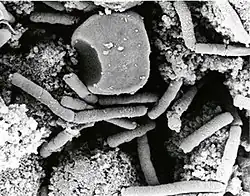

Původcem anthraxu je Bacillus anthracis, grampozitivní tyčinkovitá bakterie, která je schopná vytvářet endospory. V roce 1758 vyslovil švédský vědec Carl Linné domněnku, že původcem je tzv. furia infernalis neboli ďábelská bestie, což měl být nitkovitý červ se zakřivenými ostny po těle. Tato domněnka se ovšem nepotvrdila.

Ve 40. letech 19. století zkoumal ve městě Wipperfürthu německý doktor Aloys Pollender pod mikroskopem krev krav zasažených snětí. Objevil tak tyčinkovitá tělíska dlouhá 5 až 11 mikrometrů a o průměru asi 0,7 mikrometru. Jednalo se o první cíleně objevené mikroby. Spojitost tělísek s anthraxem byla však v následných diskusích částečně zpochybňována.

V 70. letech 19. století se anthraxem začal zabývat německý lékař Robert Koch, který tehdy působil na pruském Poznaňsku. 30. ledna 1876 se mu podařilo vypěstovat původce v moku z volského oka a poté detailně popsal životní cyklus bakterie. Při výzkumu použil průkopnicky mj. mikrofotografii. Zjistil, že mikroby vytvářejí spóry, které jsou velmi odolné a mohou přečkat dlouhou dobu v nepříznivých podmínkách.